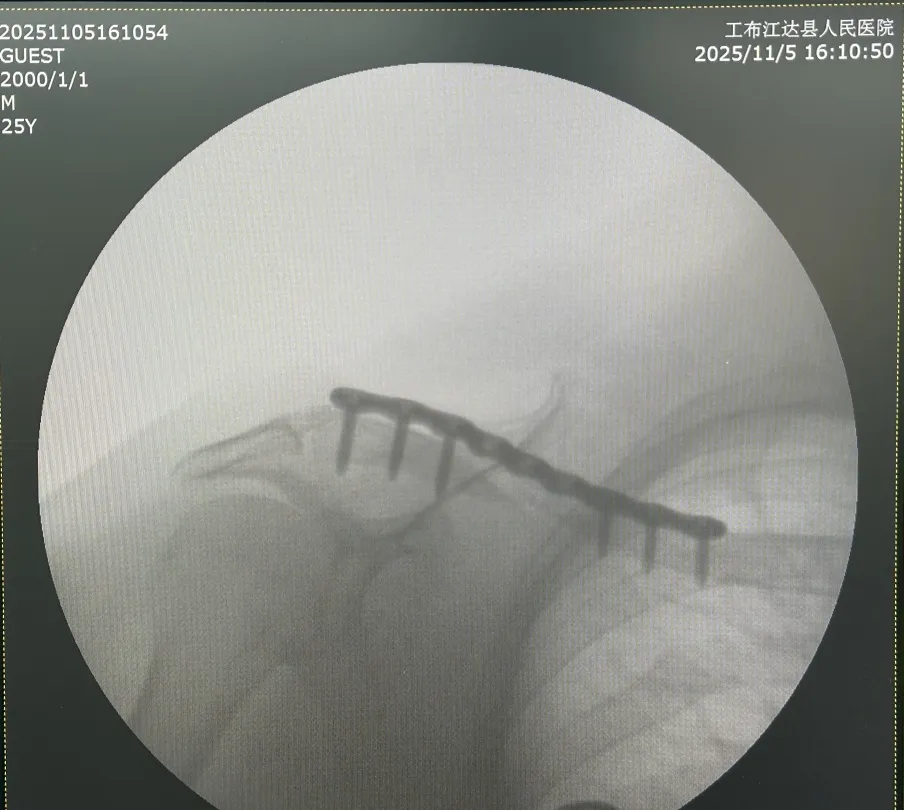

▪ 精准复位固定技术:针对患者右锁骨骨折,实施切开复位内固定术。新院区新增的C臂机提供实时精准影像支持,李伟濂医师凭借丰富临床经验,完成骨折端精准对位与内固定操作,这也是当地首次独立开展此类标准化骨科手术。